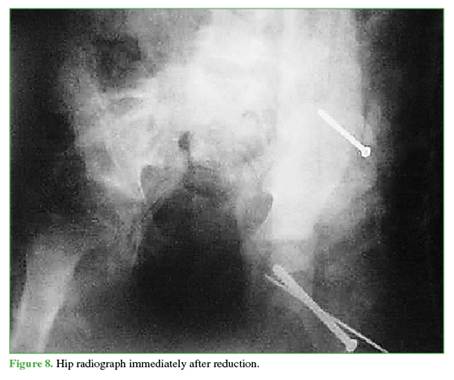

Once the hip had been drained and stabilized, another cannulated screw was inserted percutaneously to stabilize the large fragment avulsed from the iliac wing. The patient was immobilized with a hip spica cast to control the open-book component, and soft-tissue traction was applied; the patient was then placed in postoperative traction. Traction was continued for 3 weeks, and anatomical reduction of the fractures was achieved (Figures 6-8).